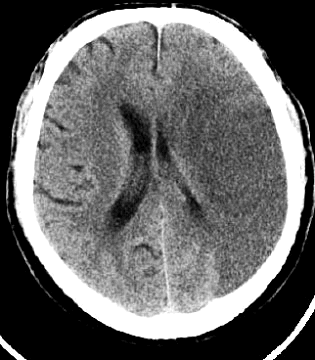

3.2) Gehirn (Não bộ),

brain

Arteriosklerose

(Mạch máu bị nghẻn), arteriosclerosis

Hirninfarkt

(Cấp tính não bộ): cerebral

infarction

Hirnblutung

(Mạch máu bị vỡ trong sọ): cerebral

hemorrhage (não xuất huyết)

Hochdruckenzephalopathie

(Auge, Gehirn, Epilepsie), High

pressure

encephalopathy (eye, brain, epilepsy),

bệnh não

cao áp.

Retinopathie

(Hư mắt): retinopathy

(bệnh võng mạc)